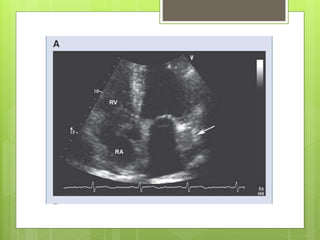

Figure 1. Transesophageal echocardiography revealed both atrial and right ventricular

enlargement (left), a defect of the partial coronary sinus (middle), and shunt of the left atrium

to the dilated coronary sinus (right) at the near longitudinal plane.

Huang X Circulation 2007;116:e373-e373